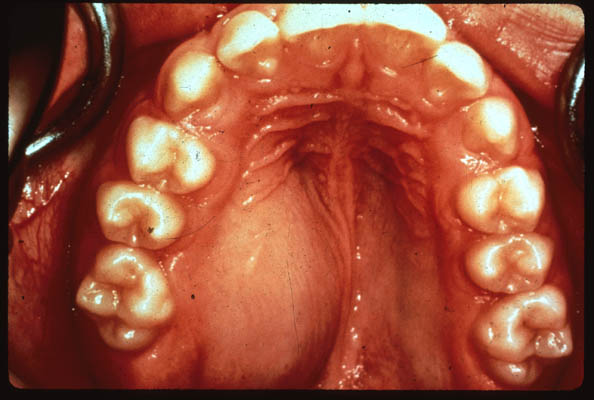

A 14 year old male presents with a complaint of an increasing painless swelling of his palate. The swelling is bony hard on palpation.

Photo of roof of mouth with swelling